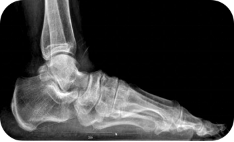

X线测量法:第一跖骨距骨角、距舟覆盖角及跟骨倾斜角等参数的测量,对足进行影像学评估。

足负重前后位、足负重侧位(足内弓角测量、外弓角测量、跟骨倾斜角)。